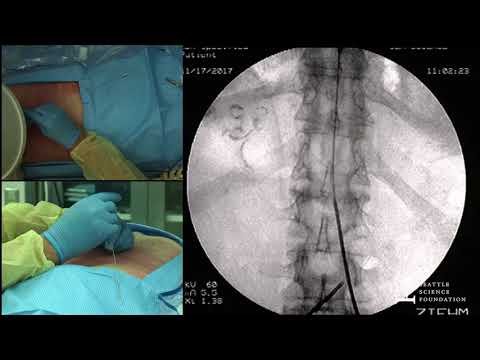

Placing a Spinal Cord Stimulator